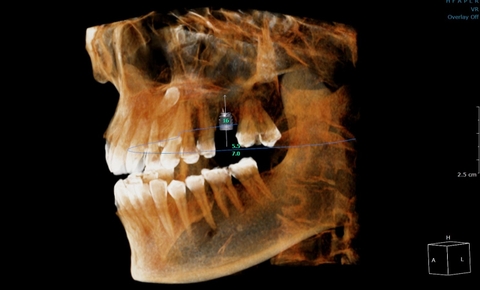

Vừa qua, bệnh nhân tới khám răng tại phòng khám đa khoa Hồng Hoàng với triệu chứng đau nhức răng. Thông qua hình ảnh chụp cắt lớp vi tính răng hàm mặt phát hiện răng số 8 mọc ngầm, và dây thần kinh nằm sát ngay răng số 8.

Hình ảnh này chỉ thấy được thông qua chụp cắt lớp vi tính (CLVT), mà các kỹ thuật chụp x quang thông thường không thể thấy được. Nếu không có chụp cắt lớp vi tính sẽ không biết được những nguy hiểm tiềm ẩn khi phẫu thuật nhổ răng số 8.

- Hình ảnh cực kỳ chi tiết, sắc nét, tránh bỏ sót các tổn thương nhỏ, bác sĩ có thể quan sát các cấu trúc như xương hàm, ống dây thần kinh, răng dưới hình ảnh đa chiều, 3D.